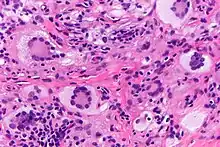

Touton giant cells, being multinucleated giant cells, can be distinguished by the presence of several nuclei in a distinct pattern. They contain a ring of nuclei surrounding a central homogeneous cytoplasm, while foamy cytoplasm surrounds the nuclei.[4][5] The cytoplasm surrounded by the nuclei has been described as both amphophilic and eosinophilic, while the cytoplasm near the periphery of the cell is pale and foamy in appearance.[6]